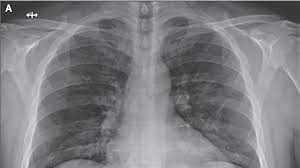

Symptoms remain mild in 85 percent to 89 percent of cases, but 11 percent to 15 percent of cases progress to severe and critical symptoms. These patients will have respiratory distress, the development of pneumonia, and even the presentation of hypotension or septic shock.